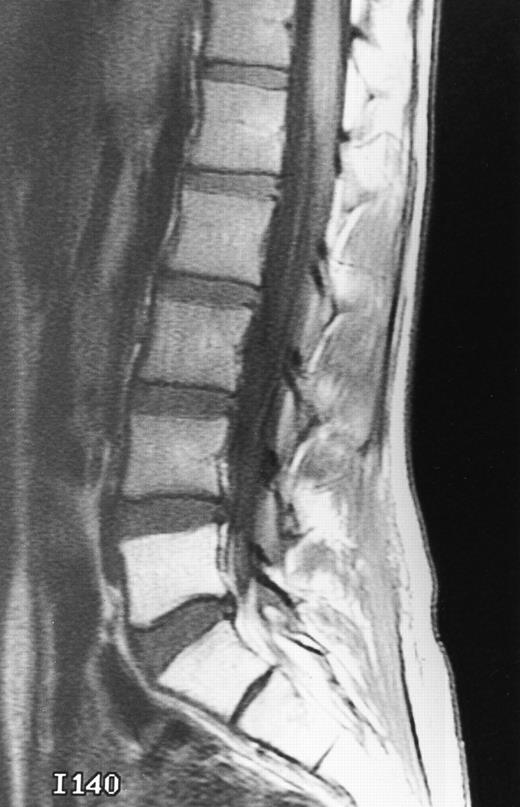

Normal appearance of spinal bone marrow in a 45-year-old woman: T1-weighted (500/11, TR/TE) (A) and T2-weighted, fat-suppressed fast spin echo (4000/96, TR/TE, ET 16) (B) sagittal MR images of the lumbar spine. Note increased signal of the vertebral bodies, relative to the intervertebral discs in (A) and increased deposition of fatty marrow around the basivertebral veins (arrowheads). On the T2-weighted image, normal intervertebral discs are brighter than the vertebral bodies; low signal in the L4-L5 and L5-S1 discs is due to degenerative changes (arrows).